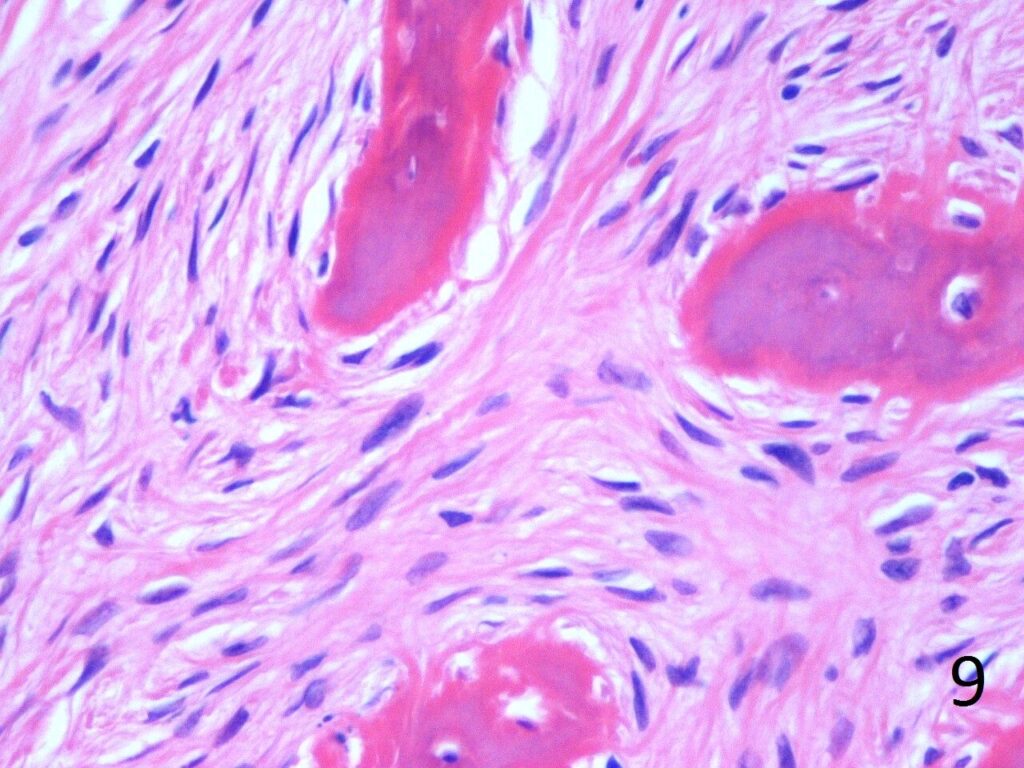

• Combination of bland hypocellular fibrous tissue with small fragments of woven bone without visible rimming by osteoblasts(Fig. 7-8) .

• Trabeculae are not lined with oteoblasts.

• No cytologic atypia is seen

Fig. 9. High power photograph of pathology of fibrous dysplasia shows woven bone being produced by the fibrous tissue. There are no osteoblasts lining the bone.